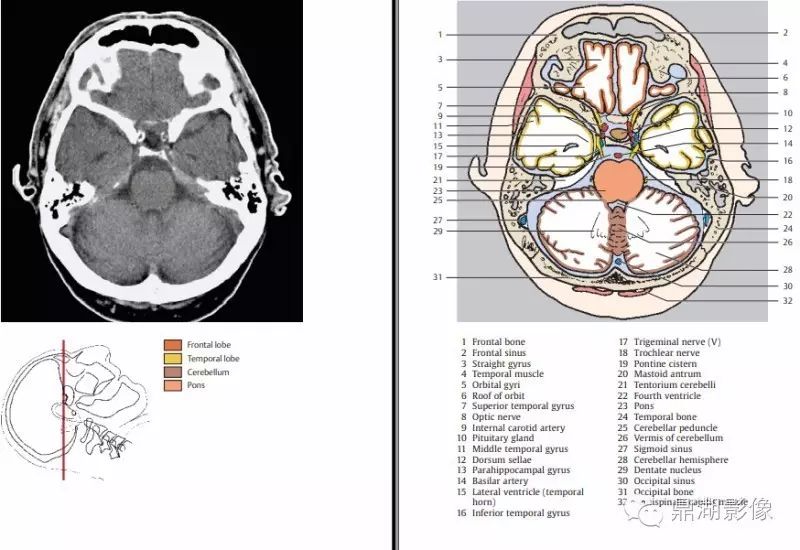

3c50a5c6b585d5264aacb398f3956fe1.jpg

1.额骨 2.额窦 3.直回 4.颞肌 5.眶回 6.眶顶 7.颞上回 8.视神经 9.颈内动脉 10.垂体 11.颞中回 12.鞍背13.海马旁回 14.基底动脉 15.侧脑室(颞角) 16.颞下回 17.三叉神经 18.滑车神经 19.脑桥池 20.乳突窦21.小脑幕 22.第四脑室 23.桥脑 24.颞骨 25.小脑脚 26.小脑蚓 27.乙状窦 28.小脑半球 29.齿状核 30.枕窦 31.枕骨 32头半棘肌